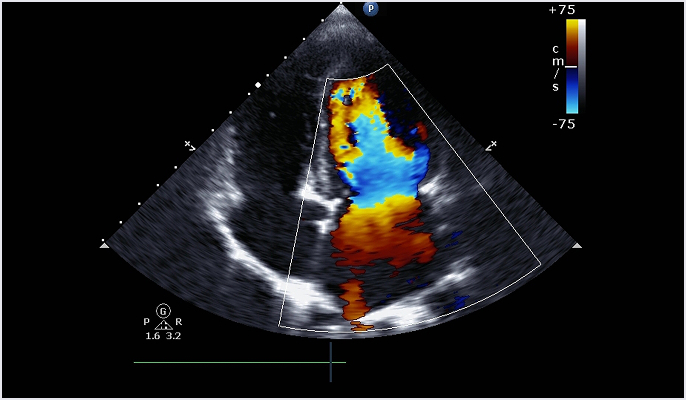

심장 초음파란?

심장에 초음파를 발사하여 심장의 구조, 크기, 기능을 실시간으로 평가하는 검사입니다. 통증이나 위험 없이 심장 내부를 직접 관찰할 수 있어, 판막질환, 심근병증, 협심증, 심근경색 등 다양한 심장질환을 진단할 수 있습니다.

진단 범위